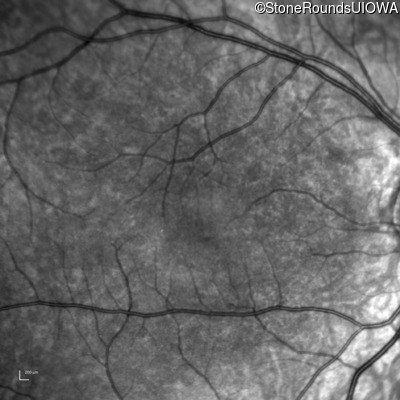

Infrared Fundus Photograph - Right - 10/160 sc

Exemplar

Infrared Fundus Photograph - Left - 10/200 sc